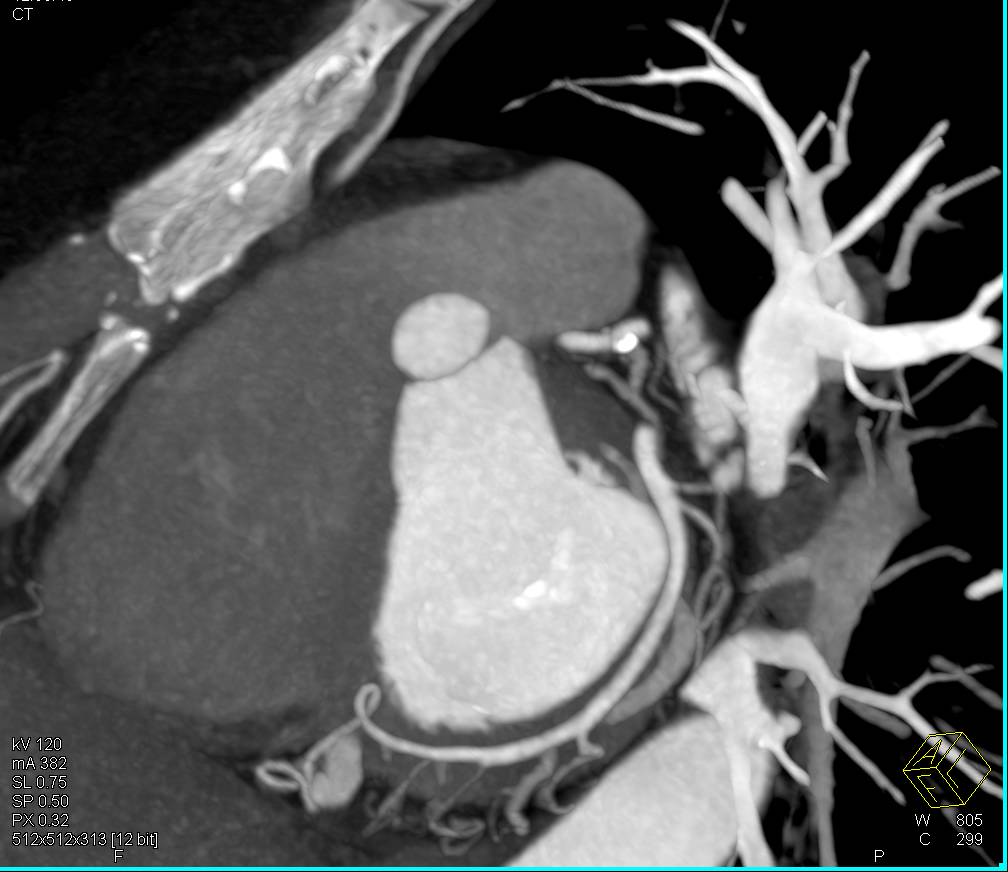

Vascular Canal Created for Bypass